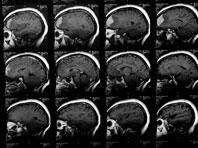

Сканирование мозга поможет определить вероятность развития наркомании у подростков

Известно, что дети, набирающие высокие баллы в тестах на поиск новизны, склонны к злоупотреблению наркотиками. Ученые из Стэнфордского университета и Университетского медицинского центра Гамбург-Эппендорф утверждают: новый тест позволяет оценить риск...